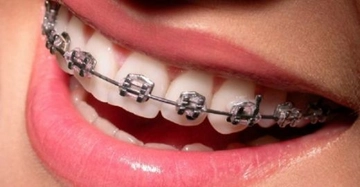

Diş Teli Çeşitleri Diş teli, ortodontik tedavi süreçlerinde kullanılan ve dişlerin düzgün bir şekilde hizalanmasına yardımcı olan bir aparattır. Diş telleri, çeşitli malzemeler ve tasarımlar kullanılarak üretilir ve bireylerin ihtiyaçlarına göre özelleştirilir. Bu makalede, diş teli çeşitlerini, avantajlarını, dezavantajlarını ve kullanım alanlarını inceleyeceğiz. Diş Tellerinin Temel Türleri Diş telleri, genel olarak üç ana kategoriye ayrılabilir: metal diş telleri, seramik diş telleri ve lingual diş telleri. Her bir türün kendine özgü avantajları ve dezavantajları bulunmaktadır.

Metal Braketler: Bu braketler en yaygın olarak kullanılan ve diğer seçeneklere göre daha uygun fiyatlıdır. Dayanıklı ve etkili olmalarıyla bilinirler. Ancak, görünür oldukları için estetik açıdan tercih edilmeyebilirler.